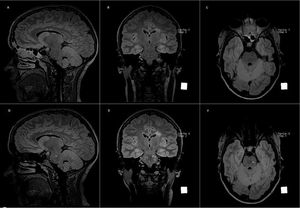

Upper row shows 3D FLAIR in sagittal (A), coronal (B) and axial (C) plane. Lower row shows 3D FLAIR in sagittal (D), coronal (E) and axial (F) plane. Lower row MR images (D, E, F) have been obtained six (6) months later compared to upper row's. Disease progression can clearly be seen in the form of new lesions in pons. Images courtesy of Bac Nguyen.